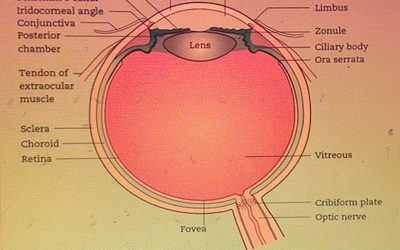

Presión intraocular, detección y opciones complementarias